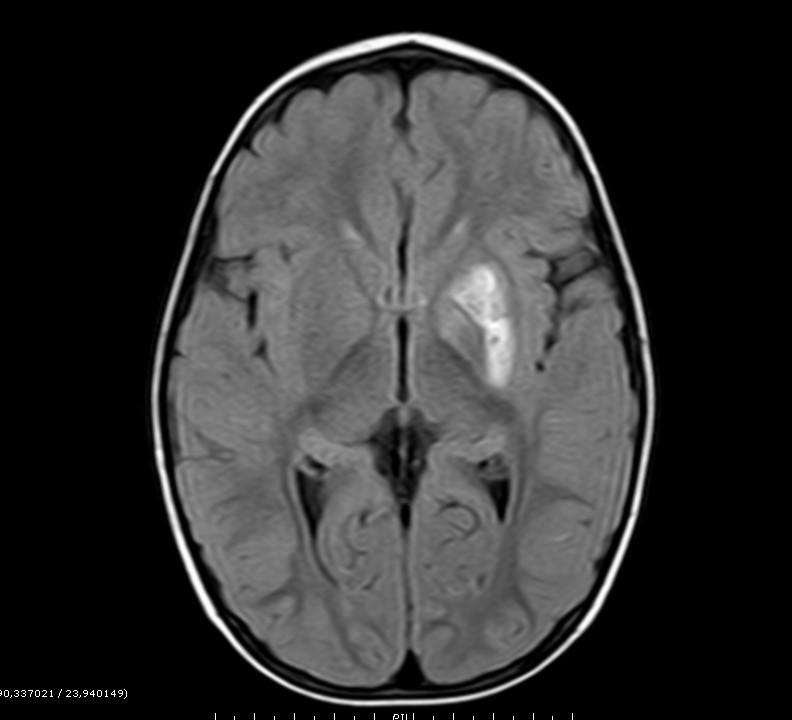

Ante la aparición de una focalidad neurológica de forma aguda/subaguda, se realizó una prueba de imagen urgente con tomografía computarizada (TC) craneal, en la que se aprecia una hipodensidad bien definida en ganglios basales izquierdos que afecta a la cabeza del núcleo caudado, el núcleo lenticular y el brazo anterior de la cápsula interna, sin edema vasogénico circundante y con tracción del asta anterior del ventrículo lateral izquierdo (hallazgos sugestivos en primer lugar de lesión isquémica antigua).

Posteriormente se realiza una resonancia magnética (RM) craneal con angiografía que nos da un diagnóstico más preciso.